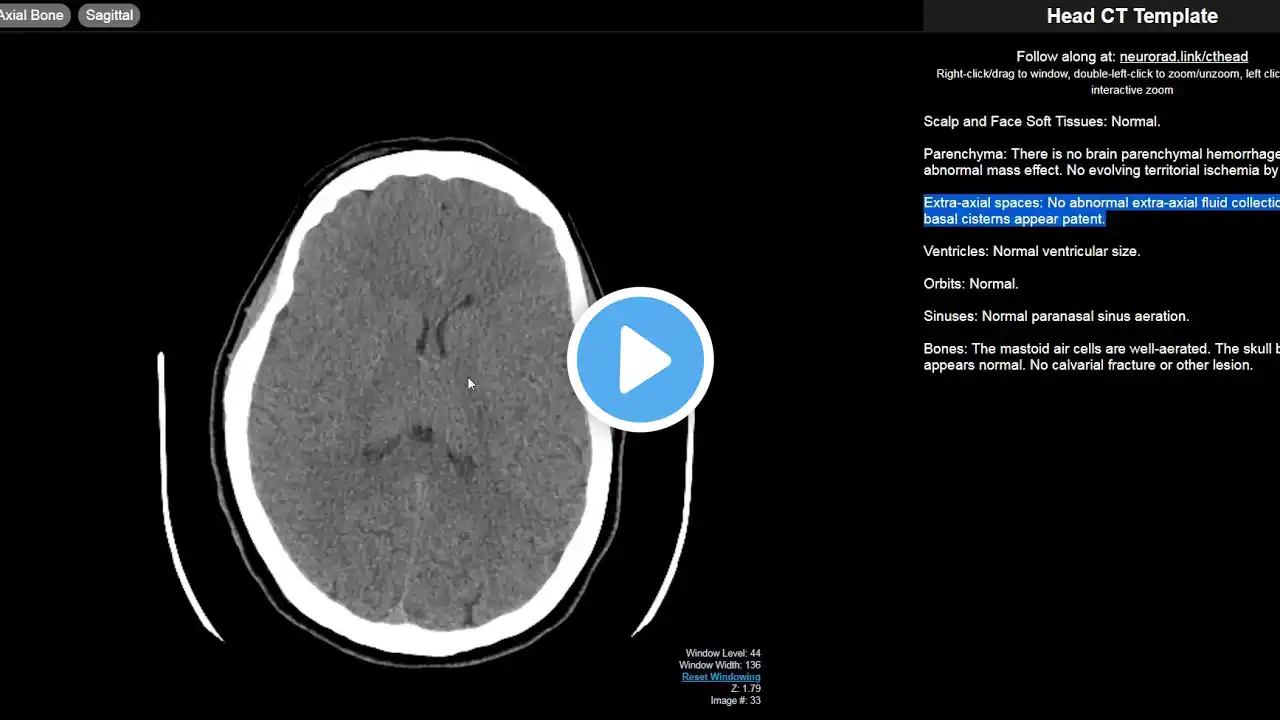

CT and MRI case-based courses at https://navigating-radiology.link/UxM... (Includes fully scrollable cases, walkthroughs of imaging findings, and comprehensive reviews of basic and more advanced imaging studies.) Video includes relevant anatomy (4:50), basic principles, approach to CT head (38:00), and multiple example cases (41:54). The goal of this video is to teach you what you need to know in order to start interpreting CT Heads right away. See http://navigatingradiology.com for more, including suggested resources.